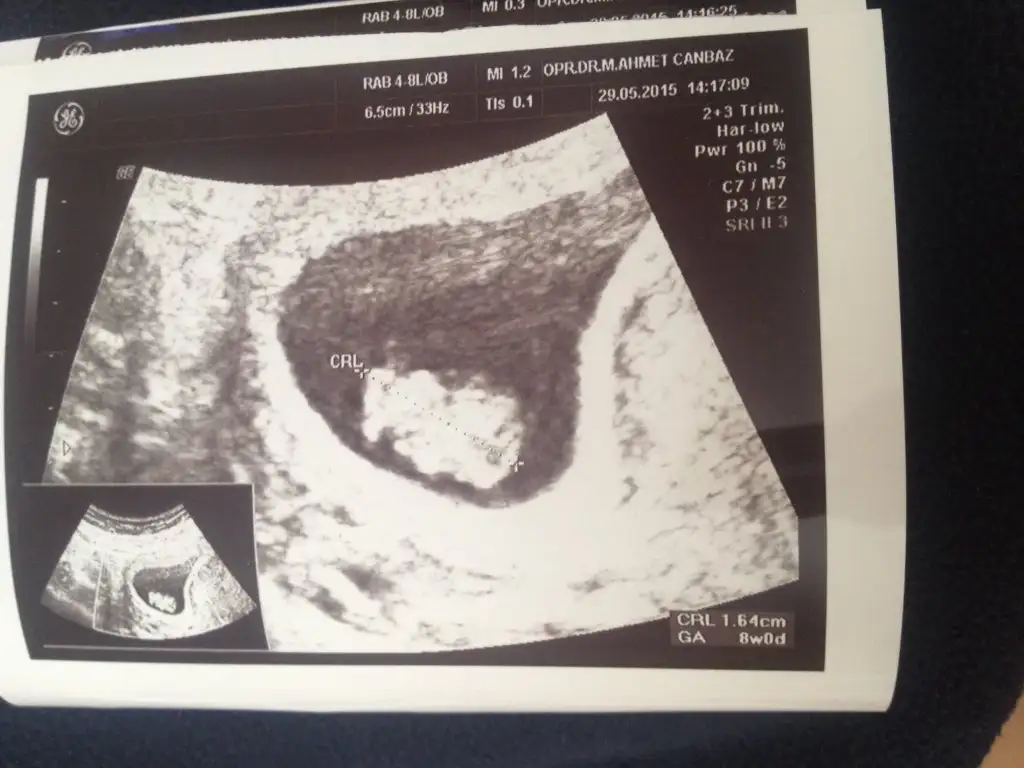

7+6 günlüğüz bugunle